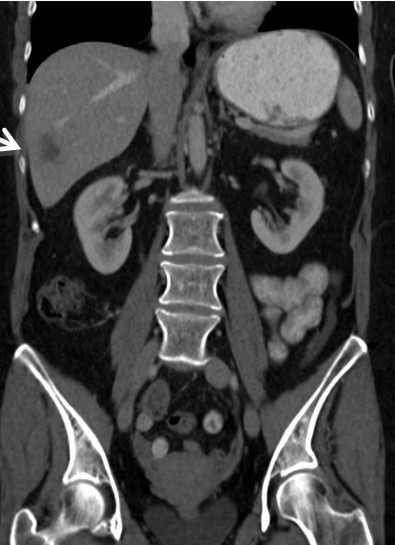

A Fifty nine-year-old otherwise healthy Caucasian female presented to an outside hospital in November 2010 with right upper quadrant pain and an enlarged gallbladder on ultrasound. She was taken to the operating room where the planned laparoscopic cholecystectomy was aborted given the identification of a segment 6 liver lesions. Biopsy demonstrated metastatic adenocarcinoma with a suspected gallbladder primary. Computerized tomography (CT) scan showed a giant gallbladder measuring about 18 cm (Figure 1). A large mass (11.0x3.1 cm) was visualized within the gallbladder with no clear evidence of invasion into liver, cystic duct or proximal common bile duct. Two hypodense, right lobe liver lesions were also present with the dominant mass measuring 2.5x1.8 cm in segment 6 (Figure 2). Preoperative tumor markers including cancer antigen 19-9 (CA 19-9) and carcinoembryonic antigen (CEA) were normal.

Figure 2. Preoperative CT scan demonstrating metastatic segment 6 liver lesion. |